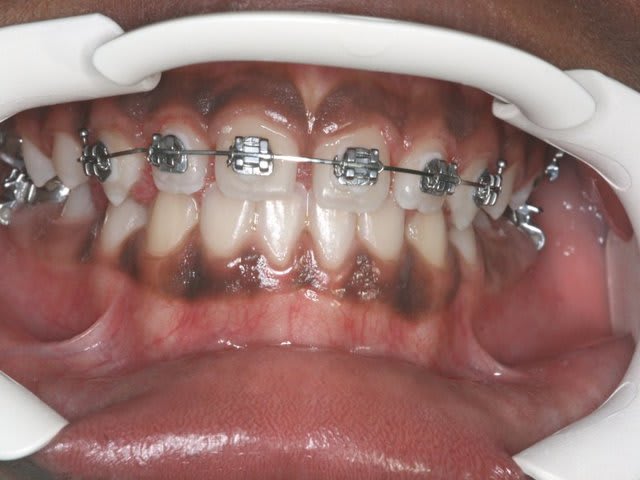

finalement, la forme d'arcade Inf. bien qu'acceptable ne me plait pas, elle ne me parait pas en harmonie avec le haut,

aussi je décide, avant de faire une surélévation d'appareiller le bas avec un B.H.

à suivre